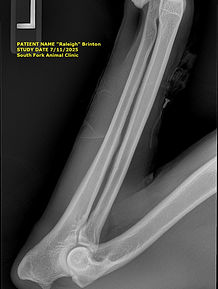

HIPS

Evaluation of the structure and alignment of a dog’s hip joints to screen for hip dysplasia. Radiographs are reviewed by board-certified veterinary radiologists through the Orthopedic Foundation for Animals, providing an objective assessment of joint conformation and stability. Passing results help reduce the risk of inherited hip disease and support breeding decisions focused on long-term mobility, comfort, and structural soundness.

ELBOWS

OFA Elbow Evaluations screen for elbow dysplasia, a painful and often inherited condition that can limit a dog’s comfort and mobility. Radiographs are reviewed by board-certified veterinary radiologists through the Orthopedic Foundation for Animals, assessing joint structure and identifying abnormalities such as fragmentation or arthritic changes. Clear elbow results help reduce the risk of passing on orthopedic disease and support breeding decisions focused on sound movement and long-term joint health.

PennHIP TestingHip health matters. A lot. Especially in Golden Retrievers.PennHIP is a specialized diagnostic screening that measures hip joint laxity, or looseness, which is one of the strongest predictors of whether a dog will develop hip dysplasia later in life. Unlike some screening methods, PennHIP doesn’t rely on a subjective pass or fail or a single static image. It provides a numerical score called a Distraction Index (DI) that objectively quantifies how stable or loose a dog’s hips truly are.

One of the biggest advantages of PennHIP is that it can be performed as early as 16 weeks of age and is designed to identify risk before degenerative changes appear. This allows breeders to make informed decisions based on a dog’s actual hip structure and genetic risk, not just how the joint looks at one moment in time.

PennHIP vs. OFA

OFA hip evaluations and PennHIP testing serve different but complementary purposes.

OFA evaluates hip conformation using a single extended-view radiograph and assigns a rating such as Excellent, Good, Fair, or Dysplastic. This assessment focuses on how the hip joint appears at maturity and whether arthritic changes are present. It is a valuable tool, especially for documenting structural soundness and long-term joint health.

PennHIP, on the other hand, measures joint laxity through a series of specialized views that evaluate how much the femoral head can move within the hip socket. This laxity is a key genetic factor in the development of hip dysplasia and cannot be accurately assessed through appearance alone.In simple terms, OFA tells us how the hips look. PennHIP tells us how the hips function under stress.

Why We Do Both

We believe relying on only one method leaves gaps.

A dog can pass OFA with a Good or even Excellent rating and still have higher-than-average joint laxity that increases their risk for hip dysplasia. Likewise, a dog may have tight, stable hips on PennHIP but not present as well on an extended OFA view due to positioning or muscle tension.

By performing both PennHIP and OFA, we gain a more complete, honest picture of each dog’s hip health. This allows us to make breeding decisions based on objective data, structural evaluation, and long-term soundness rather than minimum requirements.

Our goal is not just to meet health testing standards. It’s to exceed them. Doing both PennHIP and OFA reflects our commitment to transparency, responsible breeding, and producing Golden Retrievers who can live long, active, comfortable lives as family companions and service dogs.